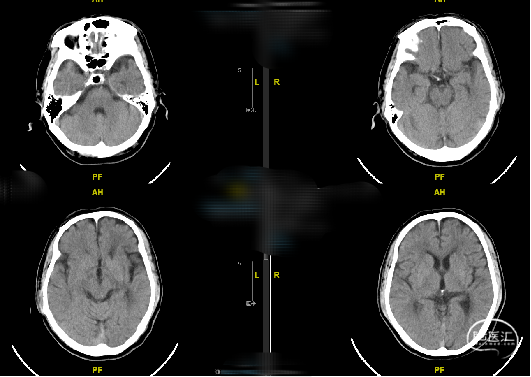

随访:患者术后一般情况好,神经系统查体无明显异常,复查头颅CT未见新发梗死/出血,血压控制良好,好转出。

随访:患者术后一般情况好,神经系统查体无明显异常,血压控制良好,术后第二天复查头颅CT未见出血/梗死并发症。